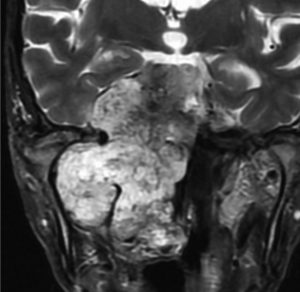

10年間さしたる症状もなく,経過観察されてきた巨大な脊索腫です。右三叉神経障害,外転神経麻痺,聴力消失などの症状が順次にでました。やがて上咽頭に腫瘍が進展して気道狭窄になりました。もともと全摘出できないものなので,主治医の先生の経過観察をできるところまでするという方針も納得ができるものです。

MRI T2強調画像(左)では等信号から高信号のまだらな境界が不明瞭な腫瘍が斜台から左海綿静脈洞内に浸潤しているのがみられます。T1強調ガドリニウム増強では,腫瘍がまだらに増強されています。トルコ鞍から鞍上部に伸び,視交差を侵し第3脳室底まで伸展しています。脊索腫が硬膜内に浸潤して神経組織と癒着することは珍しいことではありません。